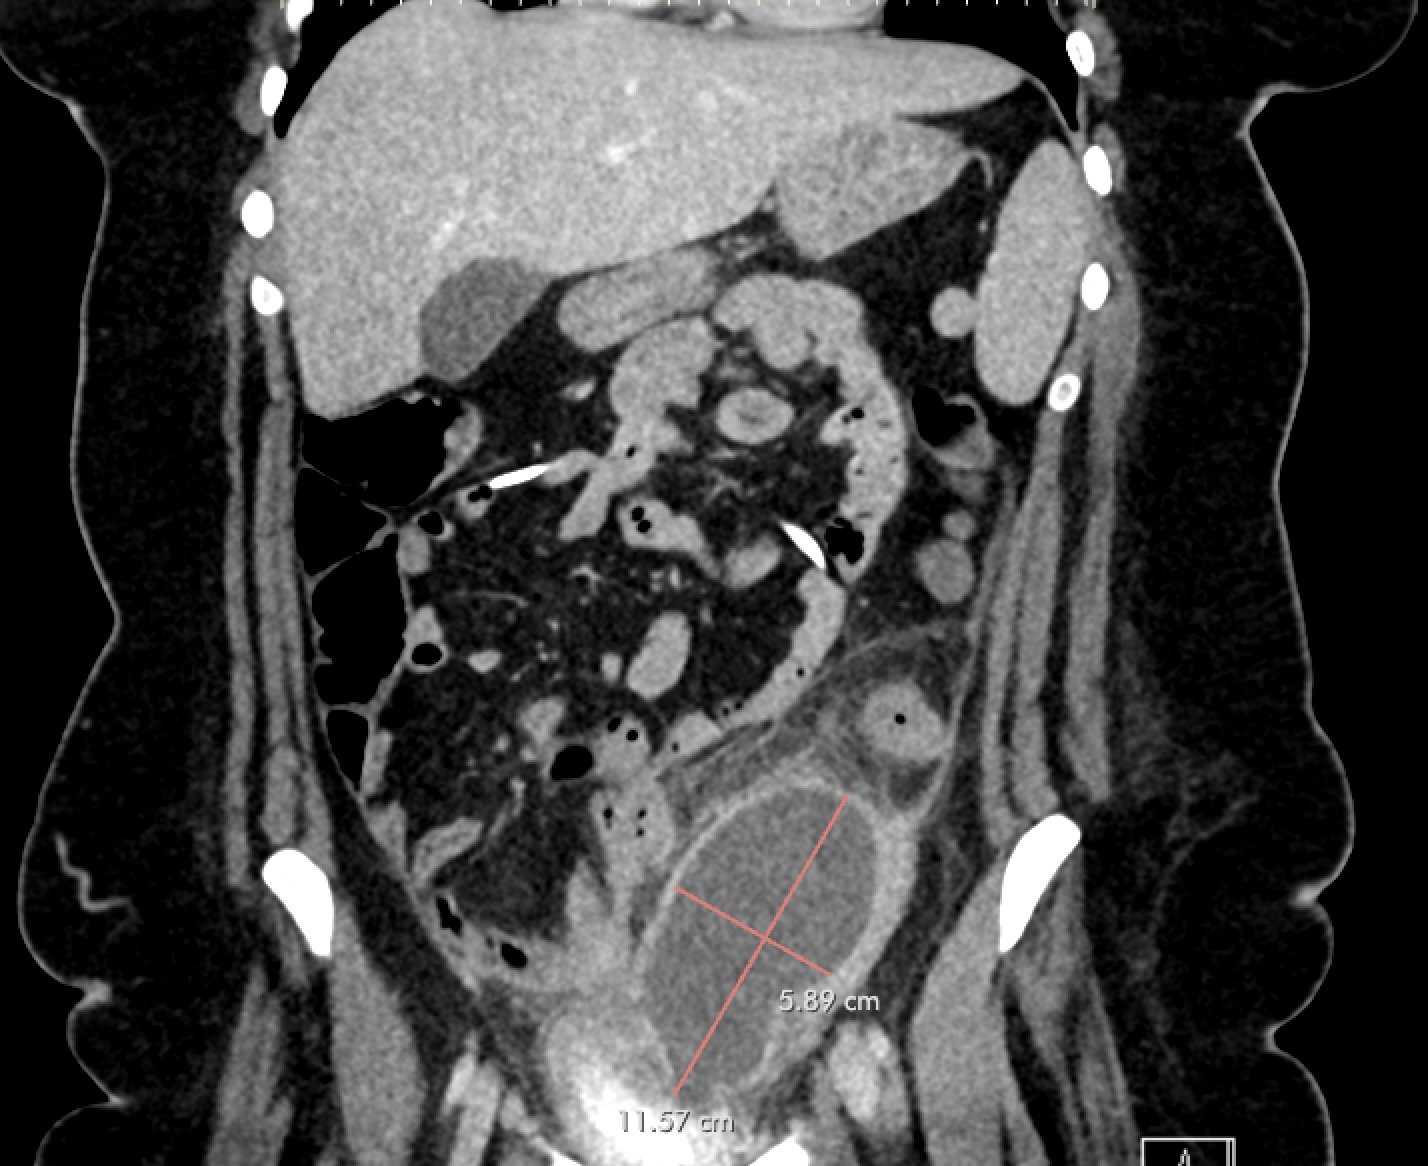

Case Presentation: A 22-year-old female with PMH of TBI with resultant hydrocephalus s/p VP shunt placement and borderline personality disorder presented with three weeks of progressively worsening abdominal pain. She also reported a new onset of vaginal bleeding for 3 days, which was different from her usual amenorrhea secondary to IUD placement. The exam was significant for tenderness to palpation in the left lower quadrant without rebound or guarding. Laboratory evaluation was significant for normal WBCs with neutrophilic predominance. CT abdomen/pelvis demonstrated a large, rim-enhancing intraabdominal fluid collection adjacent to the sigmoid colonic wall, concerning for abscess, as well as coiling of the intraabdominal portion of the VP shunt. General surgery was consulted and recommended Interval Radiology consult for drain placement. Due to location of the abscess and new vaginal bleeding, gynecology was consulted for concern for pelvic inflammatory disease and tubo-ovarian abscess. In discussion with the gynecology team, the patient reported high risk sexual activity with multiple partners in the last year with intermittent use of protection. A pelvic exam was completed and was without cervical motion tenderness or mucopurulent discharge. A transvaginal ultrasound was obtained with redemonstration of the intraabdominal fluid collection. She was started on antibiotics with cefoxitin and doxycycline for concern for pelvic inflammatory disease (PID) leading to tubo-ovarian abscess (TOA) and was admitted for further work-up and monitoring of this intraabdominal abscess. IR was consulted and a drain was placed into the fluid collection. Cultures of the fluid resulted with Hemophilus influenza, beta lactamase negative. She continued on cefoxitin and doxycycline and was stable for discharge to home to complete a 14-day course of doxycycline and metronidazole and follow-up with general surgery for drain management/removal.